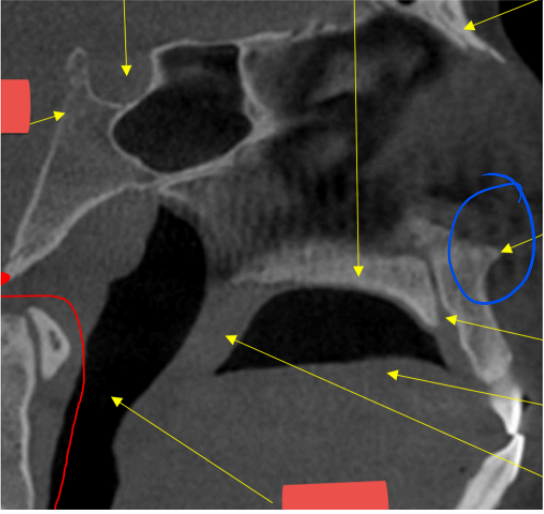

red - zygomatic process of maxilla

blue - zygoma

coronoid process

blue